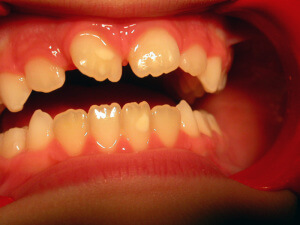

Interceptive Orthodontics

There are ways to prevent orthodontic problems and avoid braces. It’s essential to check our children early and on a regular basis, to avoid teeth crowding, discontinue a bad oral habit, or in order to guide favorably the facial and dentoalveolar development.